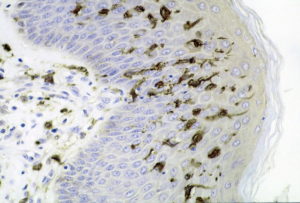

Dendritic_cells